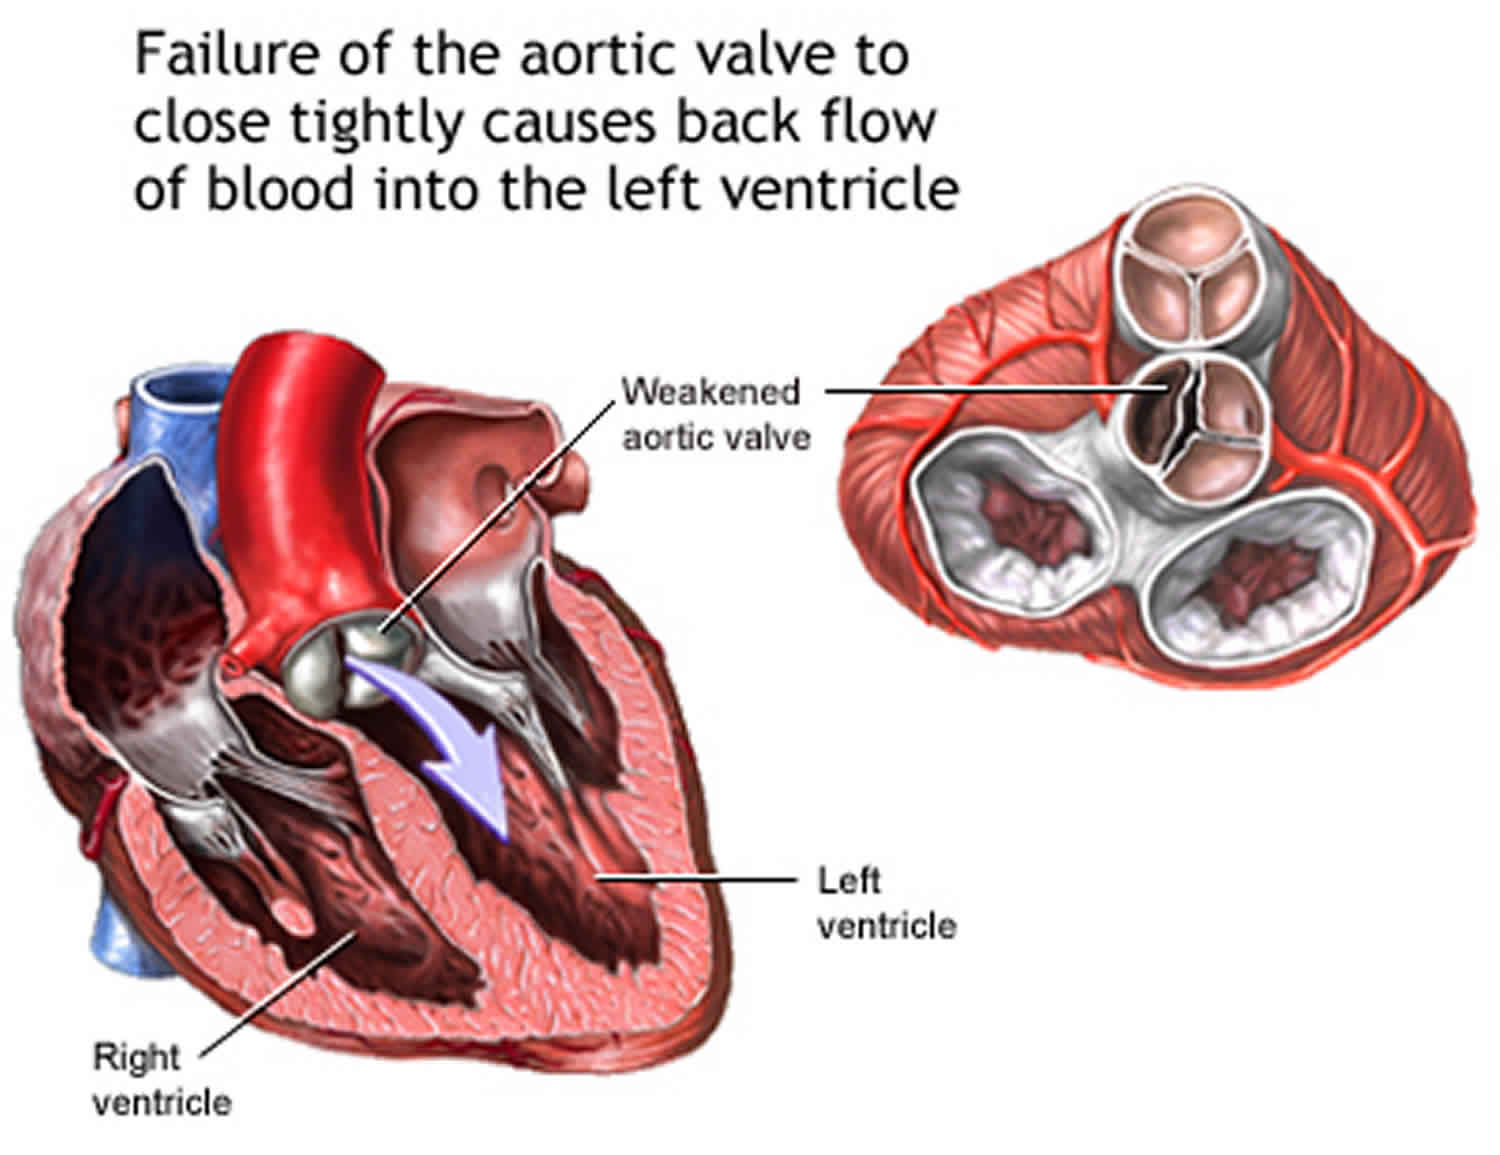

Фотографии и информация о приобретенных пороках сердца